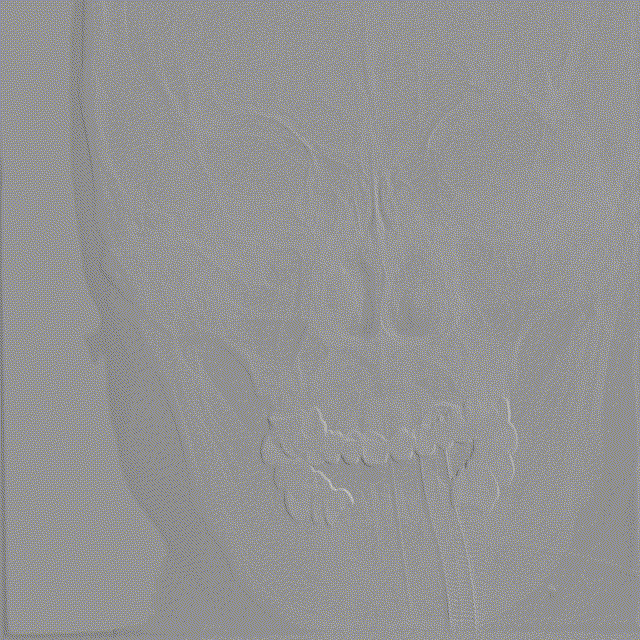

影像信息

右侧颈动脉系统造影显示:右侧颈内动脉起始段及颅内段未见狭窄;大脑中动脉显影可,远端血流速度可;大脑前动脉显影浅淡,前交通动脉未开放,右侧胚胎大脑后动脉。

左侧颈动脉系统造影显示:颈内动脉开口无狭窄,供血入颅;眼动脉段可见重度狭窄,狭窄率约70%;同侧大脑中动脉及大脑前动脉未见狭窄,前交通动脉开放代偿右侧大脑前动脉供血,左侧后交通动脉未开放。

左侧锁骨下动脉造影显示:左侧锁骨下动脉、椎动脉开口及颅内段均未见异常,基底动脉及各分支显影可。